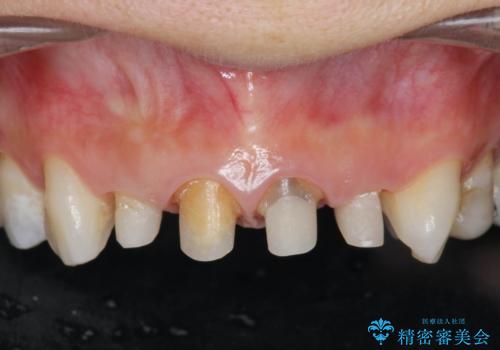

- 「黒ずんで、見栄えの悪い前歯をきれいにしたい。」と、前歯のセラミック治療を希望され来院されました。

全て根管治療のすでになされている歯の変色で、オールセラミッククラウンによる審美性の改善を計画します。

- 52.8万円(ジルコニアクラウン×4・仮歯×4)費用は治療当時の料金となります